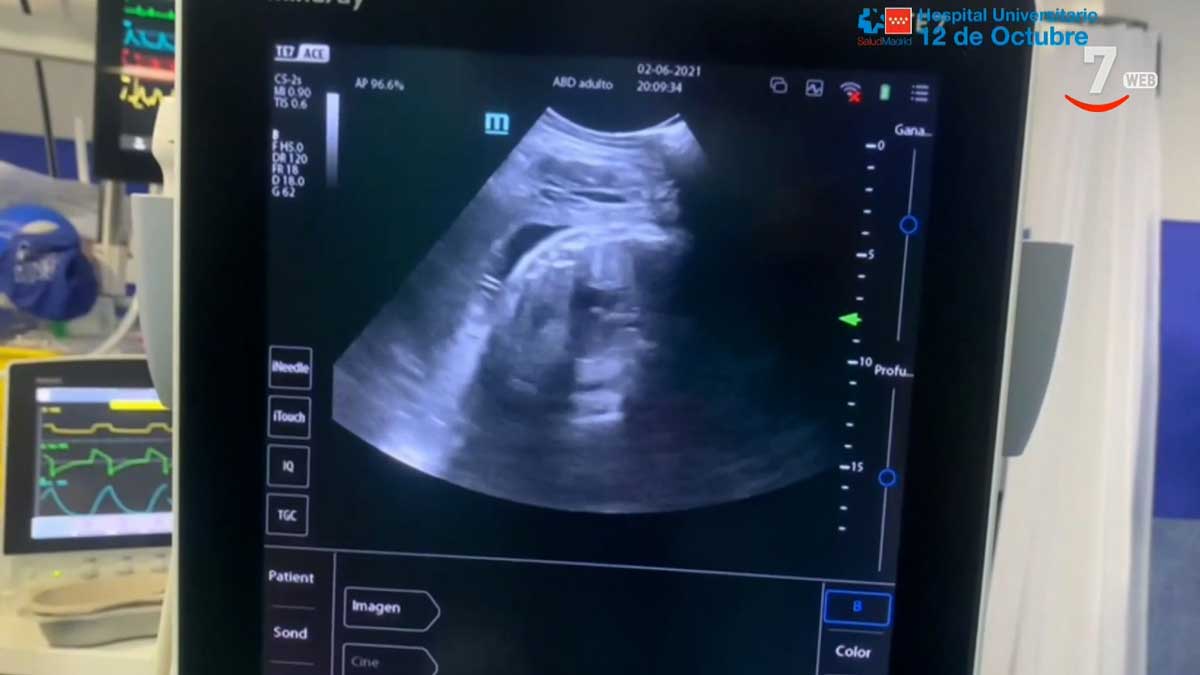

El Servicio de Medicina Intensiva del Hospital Universitario 12 de Octubre de Madrid ha utilizado con éxito un pulmón artificial (ECMO) para la recuperación de una mujer de 30 años embarazada que en el momento del ingreso presentaba neumonía bilateral por infección por COVID-19 y ha podido dar a luz a una niña.

El uso de esta técnica, junto a la supervisión de la evolución fetal por los especialistas de Obstetricia y Ginecología, y Neonatología, ha hecho posible que la paciente completara con normalidad el periodo de gestación y diera a luz recientemente y sin complicaciones a una niña, ha informado el Hospital en un comunicado.

De forma paralela, los profesionales de Obstetricia y Neonatología realizaron un manejo multidisciplinar para garantizar el bienestar de Sara y el feto, controlando su desarrollo, niveles de líquido amniótico y movimientos fetales acordes con la situación de sedación materna.